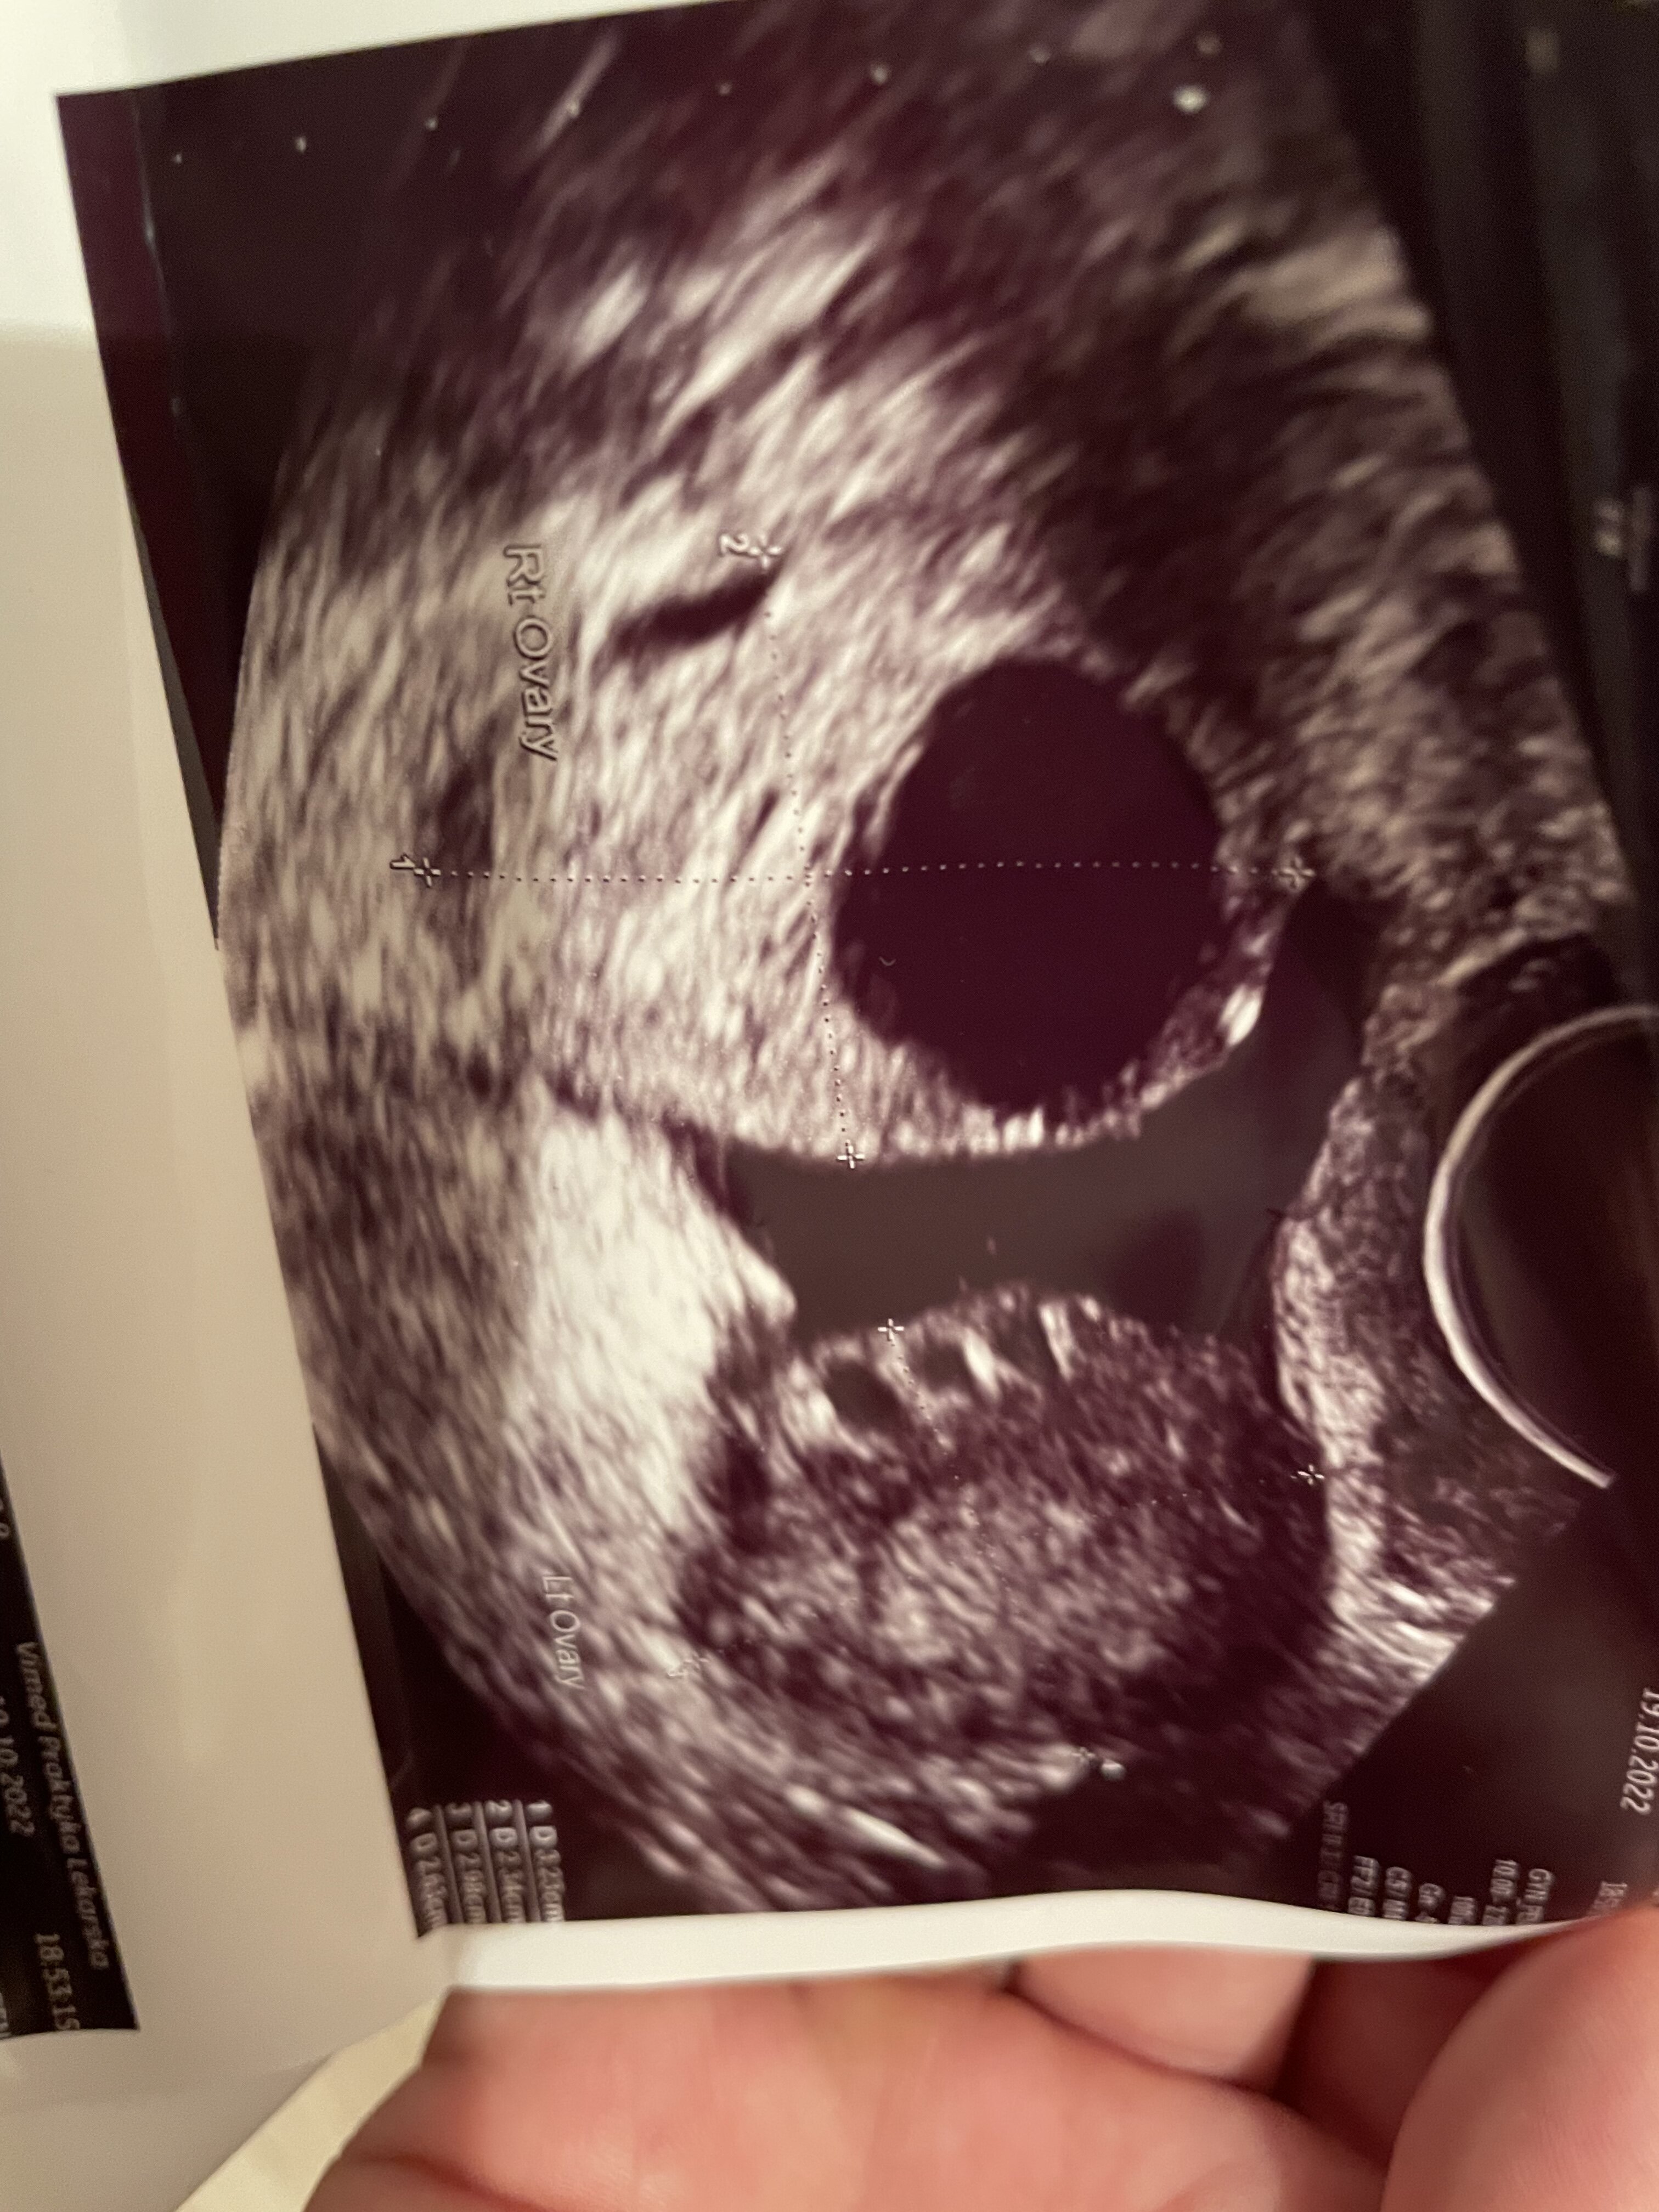

Okres dalej się nie pojawił, lekarz nie wie dlaczego. Po badaniu stwierdził ze jest płyn poza jajnikiem i nie wie skąd się wziął. Na zdjęciu macicy wydaje mi się ze widzę mały pęcherzyk ale lekarz się do tego nie odniósł. Kazał iść na betę bo może być to ciąża pozamaciczna. Jeśli beta wyjdzie ujemna to będę zagadka. Rozkładam już ręce. Czy ktoś tez widzi ten pęcherzyk czy to już tylko moje fanaberie ? Pozdrawiam

• 3752A9F5-3FEA-4F47-BB3A-B078DF8FF513.jpeg

3752A9F5-3FEA-4F47-BB3A-B078DF8FF513.jpeg

1,6 MB · Wyświetleń: 160